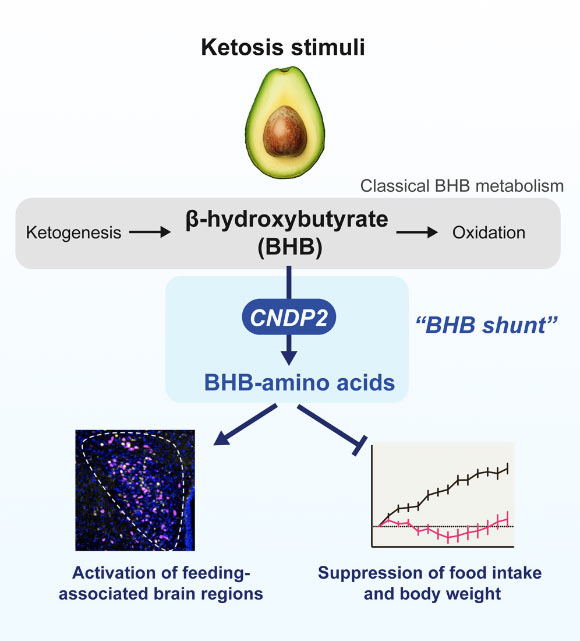

Historically, β-hydroxybutyrate (BHB) has been recognized as a hepatic substrate serving as an energy source. However, recent scientific investigation has unveiled an additional metabolic role for BHB. A specific enzyme, CNDP2, facilitates the conjugation of BHB with amino acids. Notably, the most prevalent BHB-amino acid derivative, N-β-hydroxybutyryl phenylalanine (BHB-Phe), has demonstrated the capacity to modulate body weight and metabolic processes within experimental animal subjects.

β-Hydroxybutyrate (BHB) is a prevalent ketone body. Previously, all established metabolic pathways for BHB involved the interconversion with primary energy intermediates. Moya-Garzon et al. have identified a novel, previously unknown secondary metabolic pathway for BHB, characterized by the enzymatic conjugation of BHB with free amino acids, dependent on CNDP2. Image attribution: Moya-Garzon et al., doi: 10.1016/j.cell.2024.10.032.

A prime illustration is BHB, a ketone body whose concentration escalates during periods of diminished carbohydrate intake, such as during periods of fasting, intermittent caloric restriction, or adherence to a ketogenic dietary regimen.

In this recent investigation, Professor Yong Xu of Baylor College of Medicine, along with his research team, sought to elucidate the impact of BHB-Phe, the most abundant amino acid derivative of BHB, on feeding patterns and body mass in murine models.

Professor Xu stated, “We understood that specific neuronal clusters in the brain govern feeding behaviors, prompting us to undertake a comprehensive brain mapping initiative to pinpoint the regions activated by BHB-Phe.”

“Our findings indicated that BHB-Phe triggers neuronal populations within the hypothalamus and brainstem, thereby inhibiting food consumption and reducing body weight.”

“Conversely, mice engineered to lack the CNDP2 enzyme, and consequently deficient in BHB-Phe, exhibited increased food intake and subsequent weight gain.”